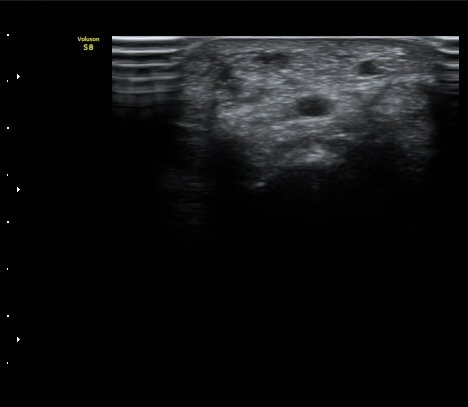

[ÆÈ²ÞÄ¡] ¿»ó ÈÄ ¹ß»ýÇÑ ¿ä°ñ½Å°æ ¸»´Ü °¨°¢½Å°æ ºÐÁö º´Áõ

ÃÊÀ½ÆÄ °Ë»ç